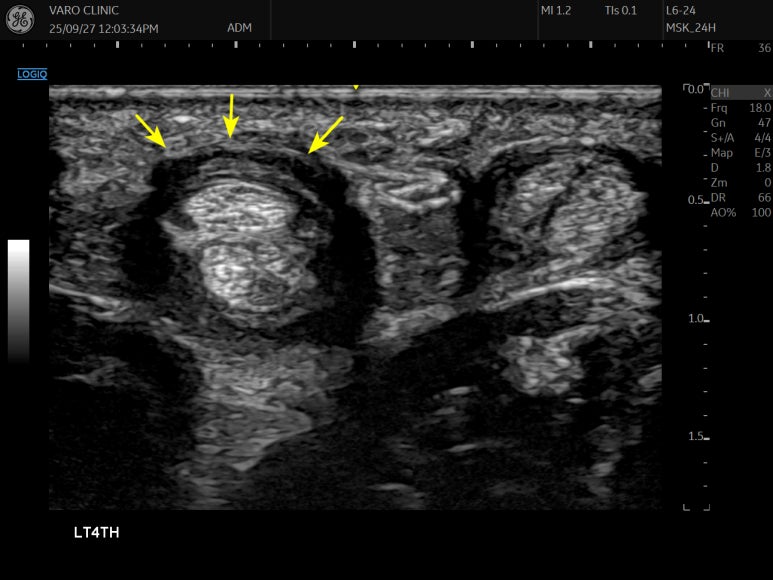

4번째 손가락의 손가락 건초염으로

내원하신 환자분의 을 손으로 촉지한 후 병변이 의심되는 곳에 초음파 영상을 확인해 봅니다.

좌측의 4번째 손가락이,

그 옆에 위치한 다른 손가락에 비해 건초가 많이 두꺼워져있는 것을 관찰 수 있는데요 (노란색 화살표)

이 지점의 유착을 박리하고,

혈액순환을 돕기 위해 도침 시술을 진행합니다.